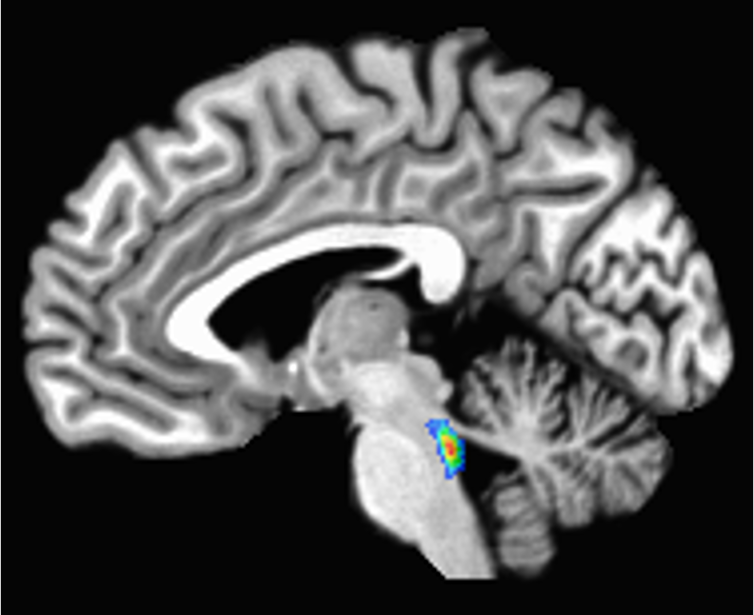

A scan of the brain with the locus coeruleus lit up in the brain stem

The locus coeruleus, which means ‘blue spot,’ is located in the brain stem, the lowest part of the brain.

Elizabeth Riley, CC BY-SA

The locus coeruleus sits in the brain stem, the lowest part of the brain. Its name, “blue spot,” comes from a pigment called neuromelanin that its cells produce.